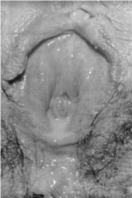

1.4.2.7.3三、临床表现